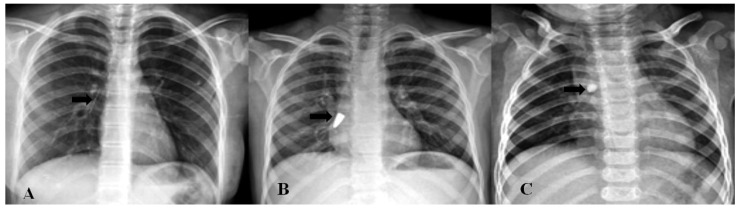

Abstract Image